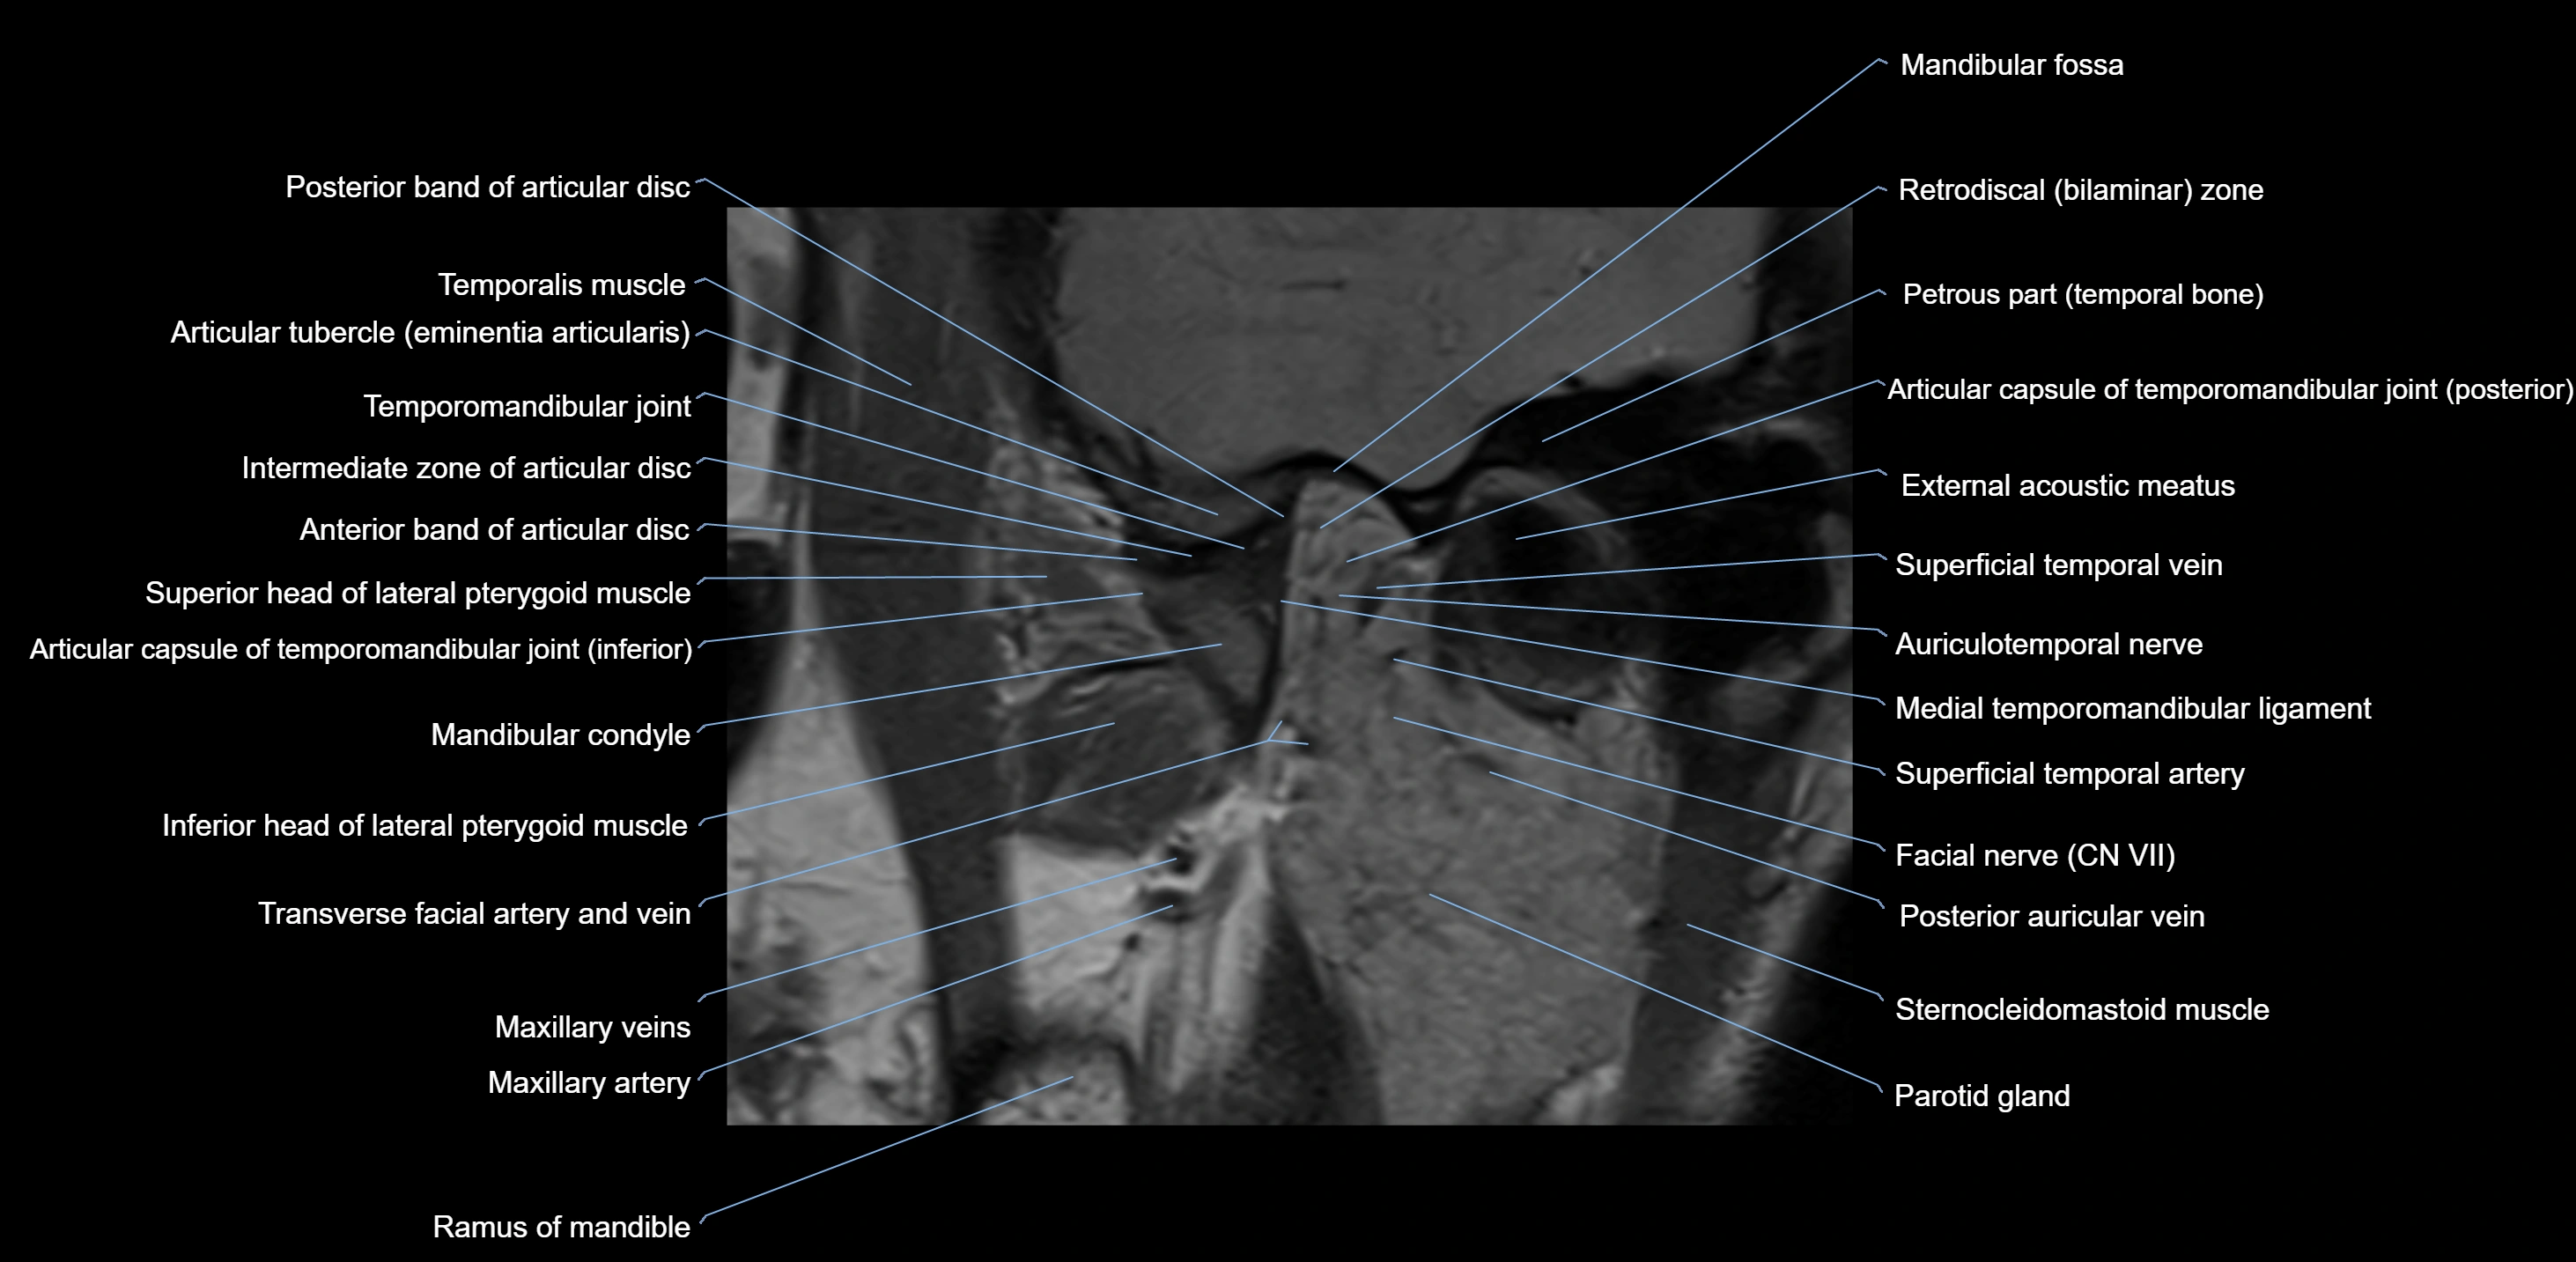

MRI appearance

T1-weighted images:

• Cortical bone: Low signal intensity

• Cancellous marrow: Intermediate to high signal depending on fatty content

• Teeth: Signal void structures

• Adjacent soft tissues: Normal gingiva and oral mucosa signal

T2-weighted images:

• Cortical bone and teeth: Low signal

• Marrow: Intermediate signal